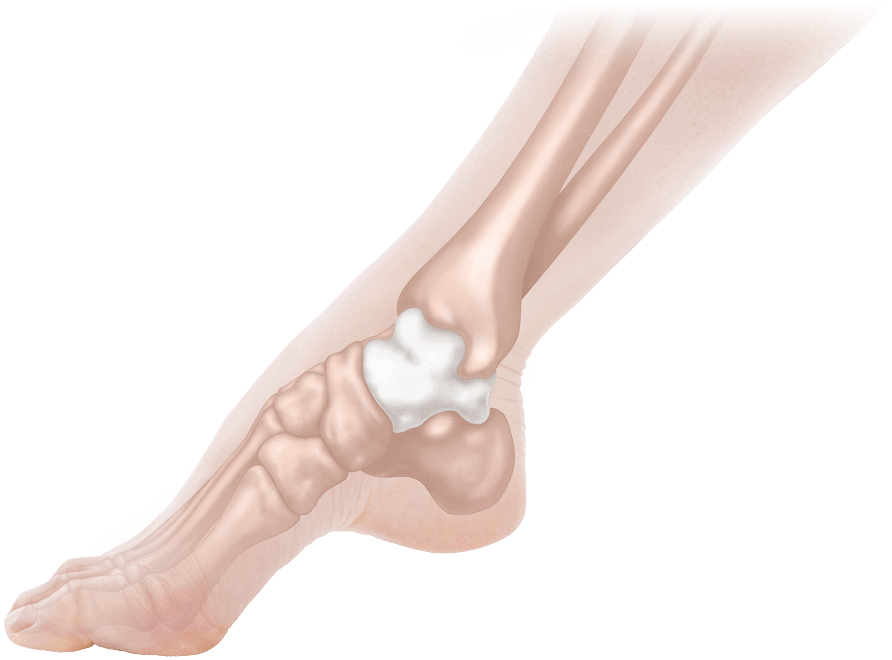

志水式整体では、人間の土台である「骨盤」と「足元(距骨)」をセットに考え、整えることにより、重力に負けない対応力を取り戻す「究極の土台調整」を行っております。

慢性的な膝や腰の痛み、頭痛、肩こり、外反母趾、骨盤の歪み、婦人科系疾患、慢性疲労、不眠、カラダのたるみ、便秘と多様な悩みに苦しむ方をこれまで施術してきましたが、どの方も共通していたのは「距骨」が歪んでいたことでした。 日常的な様々な痛みや症状の原因は、この土台である距骨にあるのです。

距骨を整える事により痛みの無い健康なカラダを取り戻して行きます。